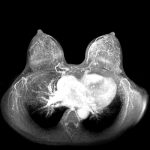

検査3乳腺MRI検査

乳腺MRI検査は、MRI検査に造影剤を利用して乳がんの探索を行う検査です。

乳房にできた腫瘍と正常な乳腺組織とを鑑別できます。

エコー検査、マンモグラフィ検査と比べて乳がんの発見率は高く、通常は乳がん発見後の精密検査として用いることの多い検査です。

MRI検査は、マンモグラフィや超音波検査ではとらえられない微小な病変を確認できる検査です。 ハイリスクの方には、MRI検診を行うことが考慮されます。